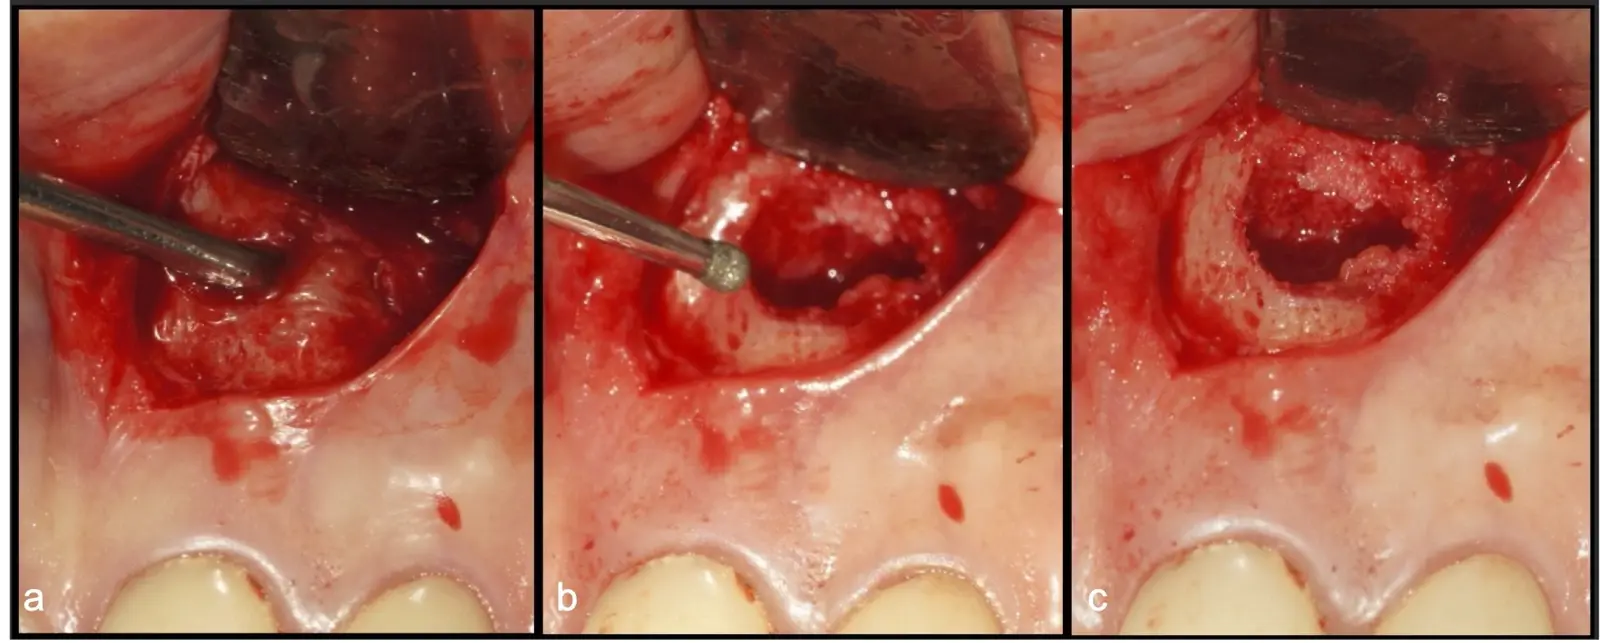

El procedimiento se inicia colocando anestesia y elevando un colgajo mucoperióstico a espesor completo y exponiendo la zona. En seguida se realiza la enucleación de la lesión, eliminando o creando una ventana en la lámina cortical que contiene el área del ápice.

El procedimiento se inicia colocando anestesia y elevando un colgajo mucoperióstico a espesor completo3 (incisión semilunar o intrasurcular con/sin protección papilar) y exponiendo la zona. En seguida se realiza la enucleación de la lesión, eliminando16 o creando una ventana17 en la lámina cortical que contiene el área del ápice; este retiro óseo se realiza con los insertos de forma aplanada dentada o inserto con cobertura diamantada plano o redondo, recordando ser lo más conservador posible (Figura 5).

Después de realizado el acceso e identificado el ápice, se procede a la limpieza de la zona con instrumentos manuales y/o con insertos diamantados de parte activa angulada para poder eliminar todo el tejido patológico del perímetro radicular apical y del tejido óseo circundante (Figura 6).